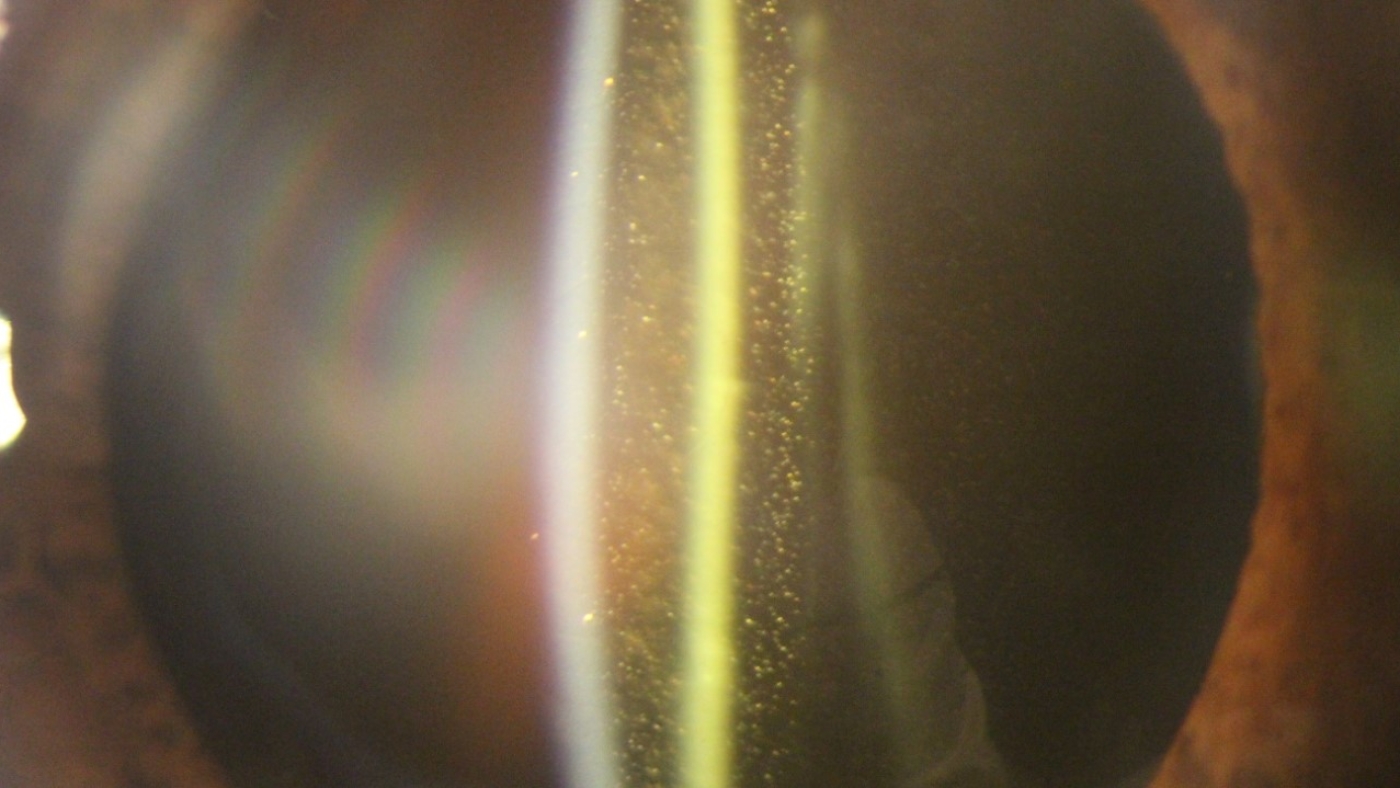

Há críticos ao modelo de Medicina Baseada em Evidências, os quais alegam tratar-se de cientificismo distante da prática diária de consultório da maioria dos colegas. Para ficar num pequeno exemplo, a foto que ilustra este post, foi tirada alguns dias atrás no consultório, sendo que, pelo interesse científico que desperta (pela descomunal quantidade de glistenings), fora publicada na última sexta-feira no site da American Academy of Ophthamalogy (Acesse pelo link).